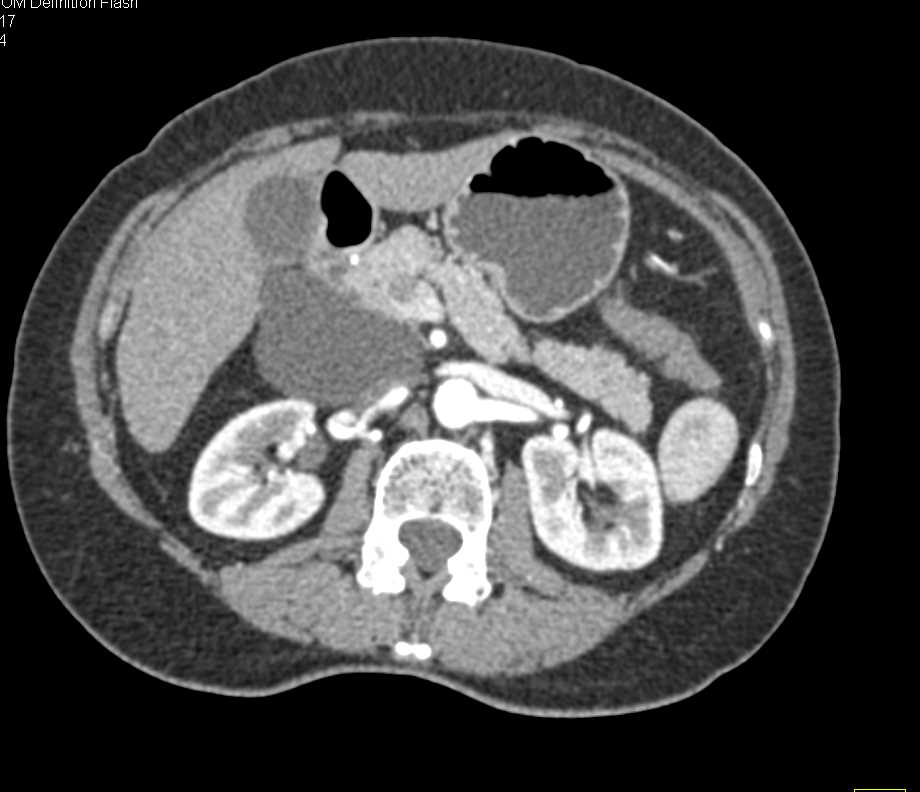

Adenocarcinoma of the Head of the Pancreas